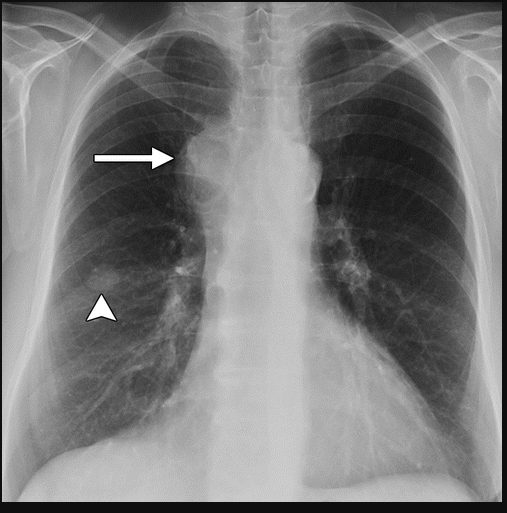

As an instance of this, the trained model was prompted in the generative setting for “carcinoma" in relation to a healthy image. The result is shown in Figure 4 alongside the real healthy scan and a separate real-case carcinoma. It is clear that the induced disease is visually comparable to that of the real case despite it’s absence from the training set. We propose that this capability arises as a result of a the internal correlation of the domain-adapted text encoder to that of the visual domain via the visual model, given that the domain-adapted text encoder is trained on the full panoply of Radiology reports.